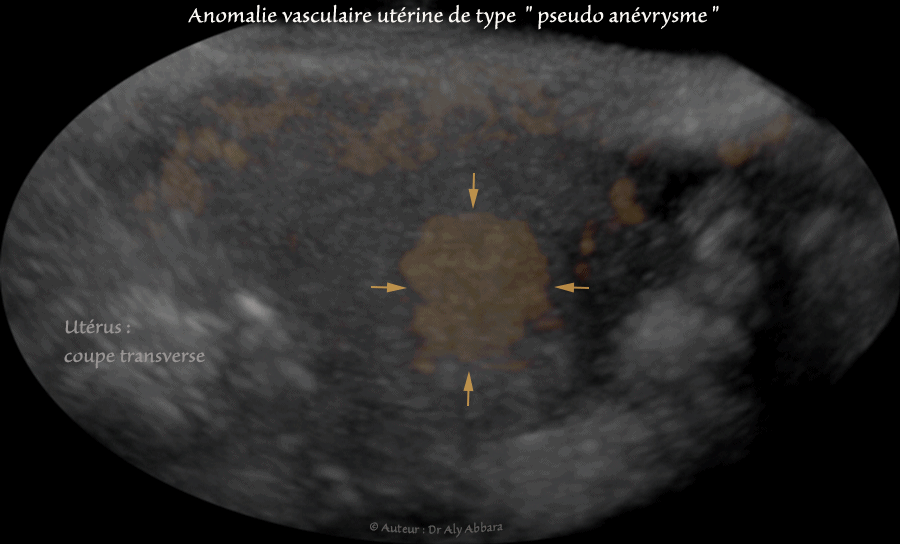

- Anomalie vasculaire utérine de type " shunt artério-veineux ou pseudo anévrysme " d'origine traumatique (accidentel) :

Doppler énergie

- Ce shunt vasculaire au sein du myomètre de la paroi utérine postéro-fundique est survenu chez une femme âgée de 28 ans, consultant, le service des urgences gynécologiques

pour métrorragies importantes (hémoglobine à 7,2 g/dl), survenant brutalement, trois semaine après une hystéroscopie opératoire et résection d'une rétention placentaire, suite à un avortement spontané ayant lieu 7 semaines auparavant.

- L'échographie met en évidence la présence, au sein de la paroi postéro-fundique de l'utérus, d'une lacune hypoéchogène à contour irrégulier. Le Doppler couleur montre qu'il s'agit d'une pathologie vasculaire débutant dans la cavité utérine et traversant verticalement les deux tiers de l'épaisseur myométriale profonde.

L'analyse du spectre-Doppler est en faveur de flux artériels tourbillonnants et se connectant à la circulation veineux située dans la couche superficielle du myomètre.

L'analyse du Doppler énergie volumique montre que cette anomalie vasculaire n'est pas connectée aux artères utérines.

- Le diagnostic retenu celui de shunt artério-veineux accidentel, ou un faux anévrysme.